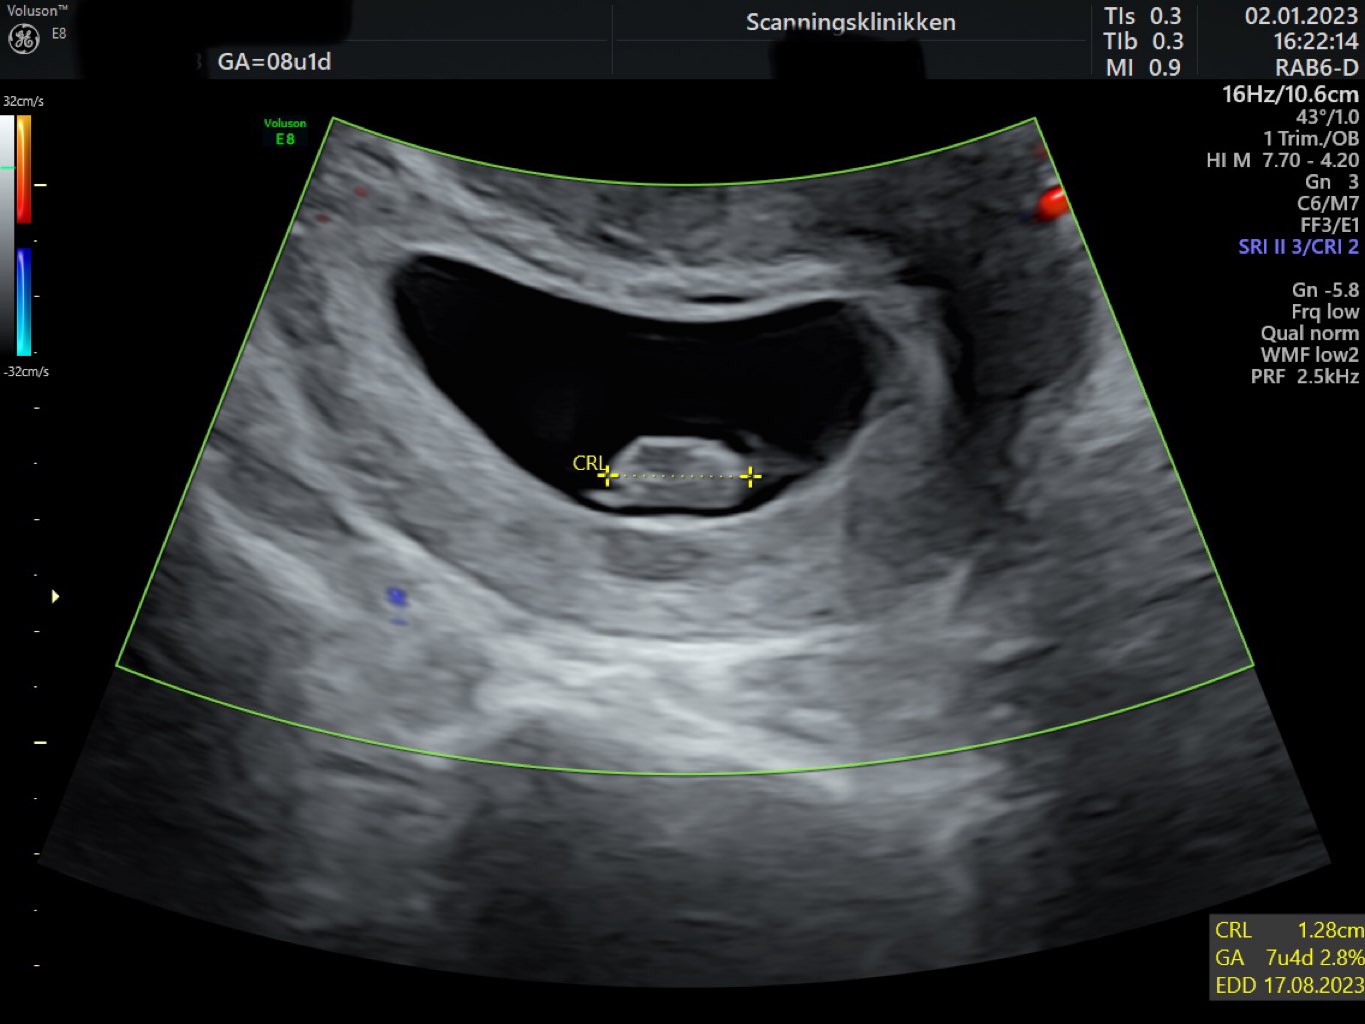

Cudowne wieści ❤️🫶🏻🔥! Ja właśnie wróciłam do domu..u mnie to 7+4 i też wszystko dobrze 🥹❤️. Maleństwo mierzy 1,28 cm 🥰.

@Paulusman Termin porodu mam obecnie na 17.08 a prenatalne 26.01 🥰

• IMG_5713.jpeg

IMG_5713.jpeg

119,6 KB · Wyświetleń: 94